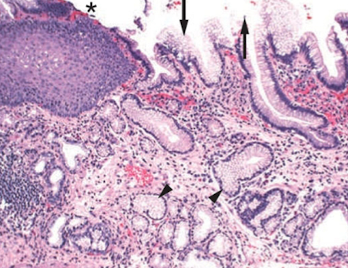

Gastric pits

in the stomach and connect to gastric glands in mucosa

lined by surface mucous cells

What makes up the gastric mucosa?

gastric gland isthmus

gastric gland neck

gastric gland base

What cells are in the gastric gland isthmus?

parietal cells

What cells are in the gastric gland neck?

neck mucous cells

stem cells (replenish cells at surface constantly exposed to stomach acid)